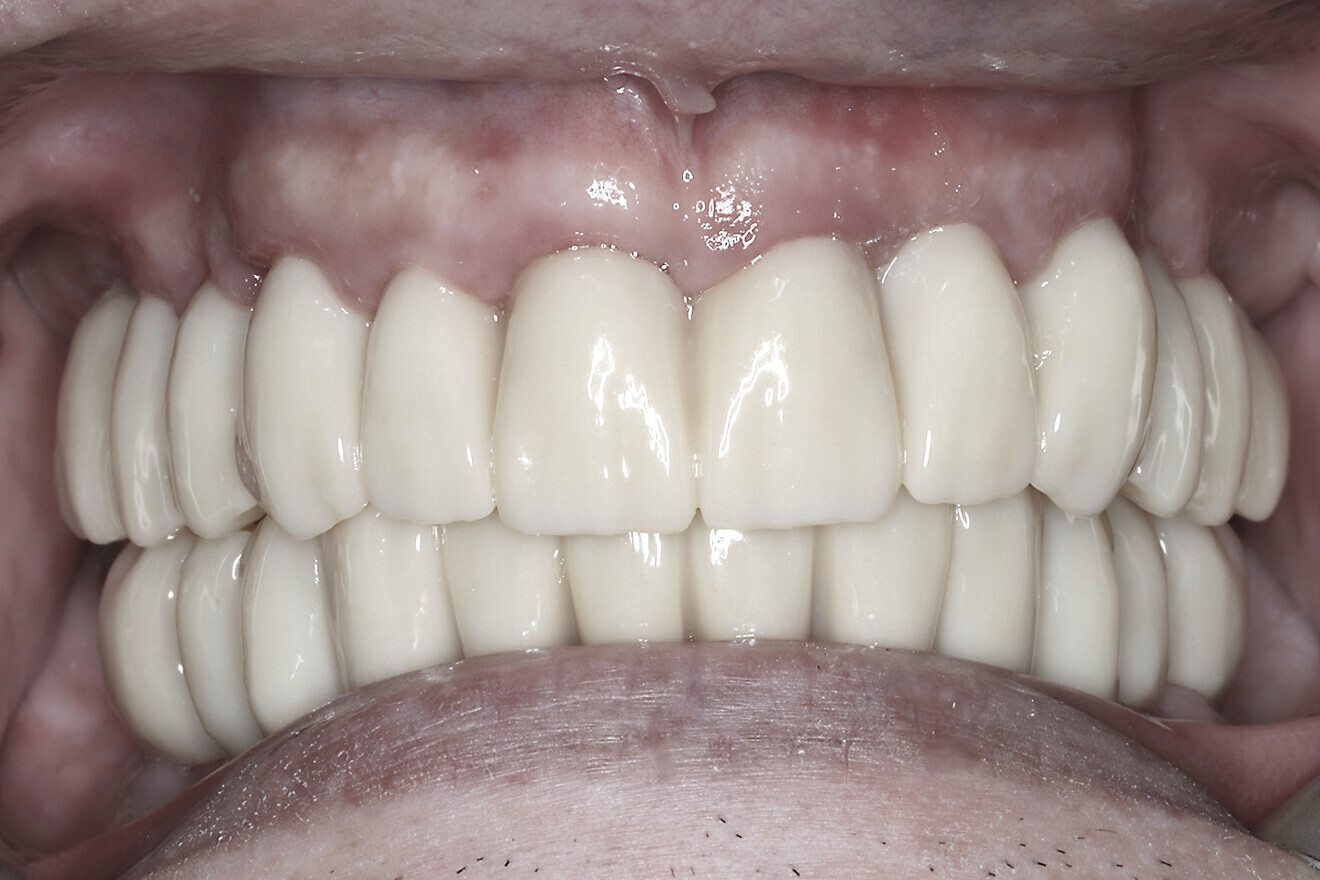

The data collected was sent through a scanning software portal (Medit Scan for Clinics) to the dental laboratory with requested changes for correction of the desired smile design. Utilising advanced planning features in the design software (exocad), the midline and tooth size changes were corrected. 3D-printed maxillary and mandibular PMMA restorations were used for try-in using the direct-to-MUA screws (Vortex LA VIS; Fig. 16a). Fit, phonetics, aesthetics and occlusion were evaluated and confirmed using digital articulation (OccluSense; Fig. 16b). The patient was extremely satisfied with the printed try-ins. Since no adjustments were required, the patient was allowed to leave with the printed try-ins as new provisional restorations made from extra-strong resin. The new provisional restorations were worn for ten days to confirm form and function. The final shade was chosen, and metal-free monolithic zirconia restorations were then fabricated by the laboratory.

Fig. 17c: Final patient smile showing excellent aesthetics and a happy patient.

The final restorations were passively and accurately seated ten days later uneventfully using Vortex LA VIS screws. Confirmation records were taken with photographs, radiographs and digital articulation to recheck fit, function, phonetics and occlusion (Fig. 17a). The patient was extremely satisfied with his final restorations, describing the process as life-changing and surprisingly fast in comparison with what he had heard about full-mouth implant therapy. He was especially pleased with the speed at which the final process was able to be completed (Figs. 17b & c).